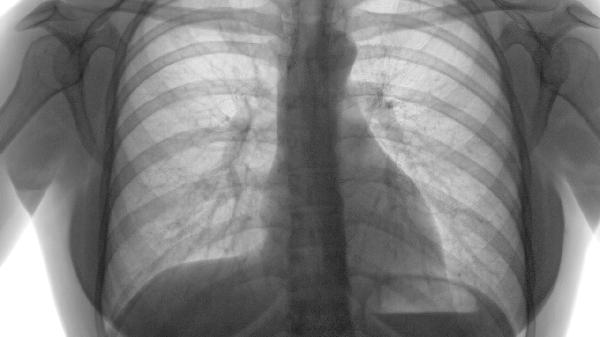

胸部呈特征性桶状胸改变,叩诊呈过清音,听诊呼吸音减弱伴散在干湿啰音。由于膈肌下移,可见肋间隙增宽和锁骨上窝凹陷。部分患者出现杵状指和口唇紫绀等长期缺氧体征。